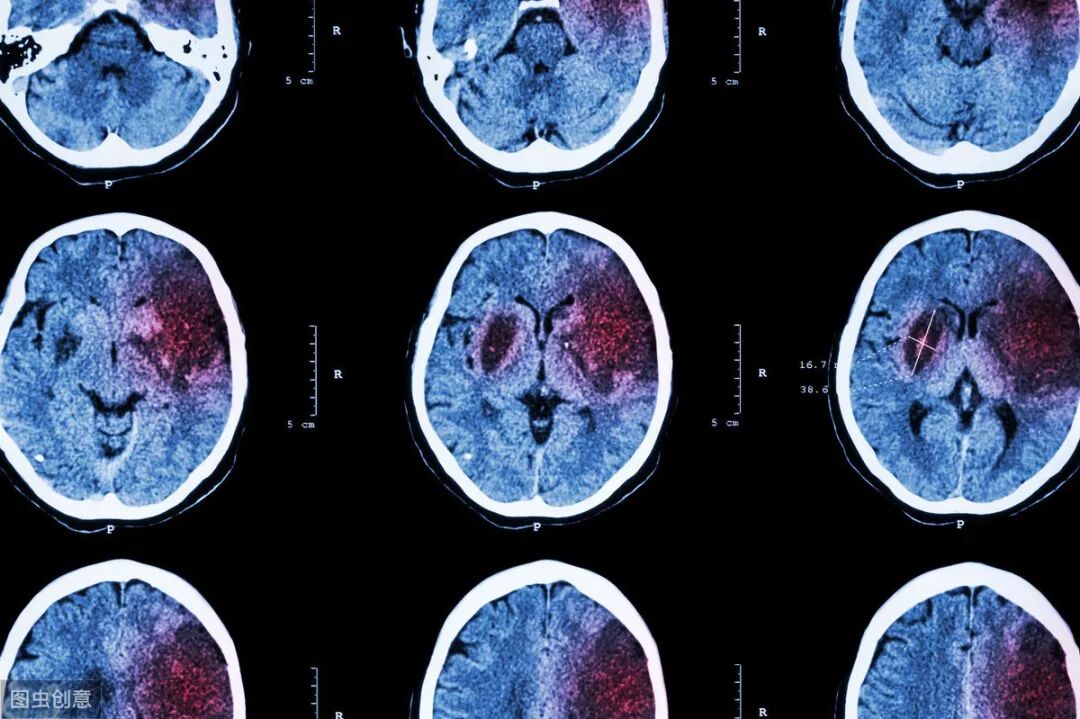

文章一开头的那个女病人,迅速做了颅脑CT,是脑干出血。

脑出血本来就很凶险,脑干出血更加是凶险中的凶险,因为人体的呼吸、心跳中枢都在脑干那里,一旦脑干出血,这些中枢都可能受到影响。

患者会迅速致死。

医生会迅速看病人的瞳孔,看看有没有反射,有没有不对等,还要检测患者的四肢肌力、肌张力情况,快速做一些神经系统的查体。最后最最关键的是,立即做头颅CT。如果有脑出血,头颅CT能第一时间发现。

但如果是脑梗塞,头颅CT就不行了,可能要等到24-48小时后才能显示出来。